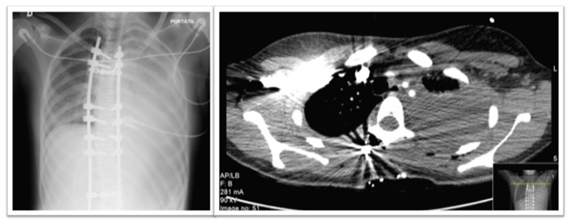

Twenty-four hours after the surgery the patient started to complain of thoracic pain with pleuritic characteristics. A blood gas analysis without oxygen supply was carried showing a hypoxemia with an arterial partial pressure of oxygen of 69 mmHg and a two-unit drop on haemoglobin. A new thoracic roentgenogram was carried and showed a massive hemothorax, which was confirmed by CT imaging. Angio-CT imaging allowed excluding pulmonary thromboembolism. Misplacement of pedicle screws was also excluded by the original CT scan (Figure 1&2).

Figure 2 On the left: thoracic roentgenogram showing a left white lung. On the right: CT image showing massive hemothorax.